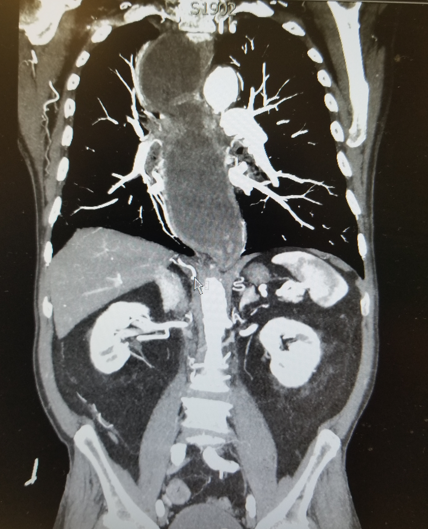

Achalasia

Cause: lack of peristalsis, failure of LES to relax. Believed to be from an autoimmune/infectious destruction of neuronal ganglion cells

Sx: dysphagia, regurgitation, weight loss, respiratory sx

Manometry findings: ↑LES pressure, Incomplete LES relaxation, No peristalsis (aperistalsis)

DX: Barium swallow: tortuous dilated esophagus, epiphrenic diverticula, “bird’s beak” appearance to distal esophagus, EGD: rule out esophageal cancer (pseudoachalasia)

Tx: balloon dilation of LES (80% effective), Nitrates, CCB

Surgery- Heller myotomy: left thoracotomy, lower esophageal myotomy, partial Nissen fundoplication